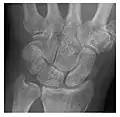

Figure 3: A 26-year-old man presenting with wrist pain after being assaulted. (a) Initial anteroposterior radiograph shows a subtle linear lucency within the scaphoid extending to the scaphocapitate articular surface that was overlooked (arrow). (b) Initial "scaphoid" view was negative. (c) Followup anteroposterior radiographs, 12 days later, shows obvious scaphoid fracture (arrows).[1]